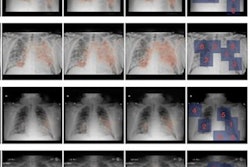

After verifying the AI lung segmentation results, radiologists then manually segmented the lung opacities and noted the opacity subtypes. Next, the researchers employed generalized temporal curves to correlate the CT data with lab measurements such as blood cell count and procalcitonin levels. 3D visualizations were also used to reconstruct the evolution of COVID opacities.

3D image visualizations show the evolution of COVID opacities over the course of the disease. Images courtesy of Nvidia.

3D image visualizations show the evolution of COVID opacities over the course of the disease. Images courtesy of Nvidia.The researchers found that lung opacities appeared in an average of 3.4 ± 2.2 days prior to symptom onset and peaked an average of 0.6 ± 3.1 days after symptoms began. Ground-glass opacity onset was earlier, and it resolved later than consolidation, according to the authors. As for lab results, lactate dehydrogenase and C-reactive protein peaked earlier than procalcitonin and leukopenia.